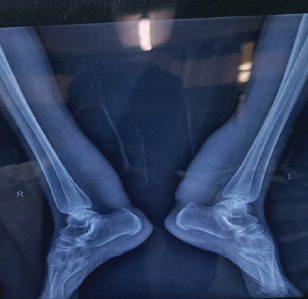

An Uncommon Case of Bilateral Ankle and Foot Injury in a Pediatric Patient Leading to Bilateral Talus Fracture

Laxman Choudhary , Amandeep Bains , Aakarsh Aggarwal , Nitesh Gahlot , Akshant Chandel , Aryan Mechu

………………………………p.130-137